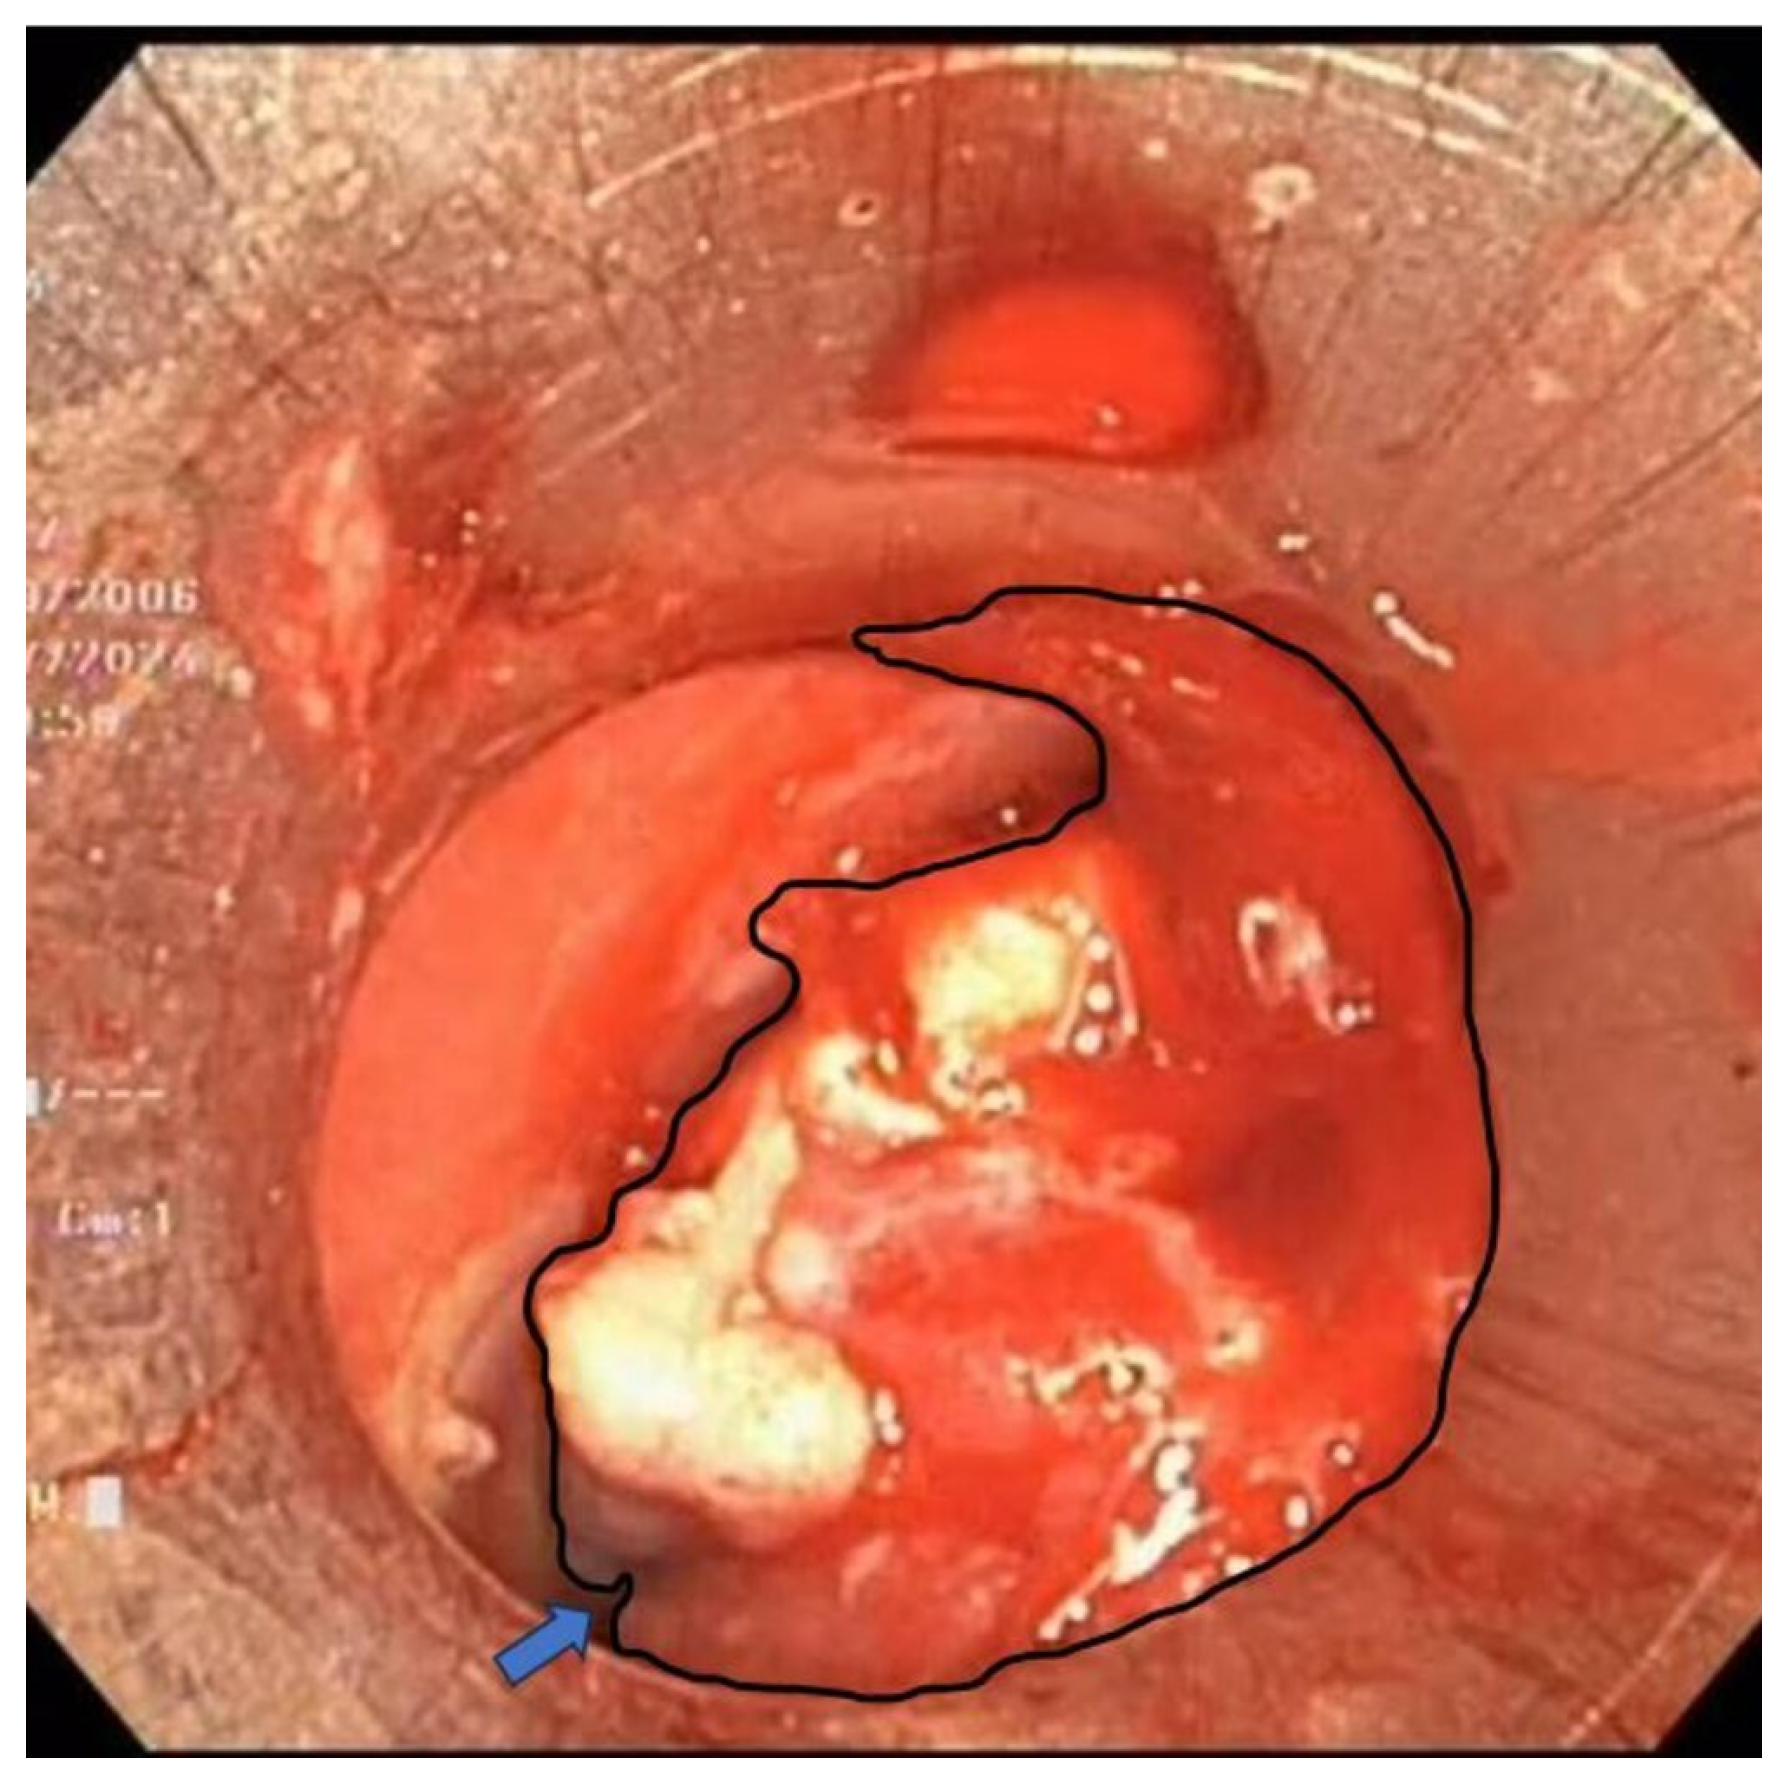

2. Case Report